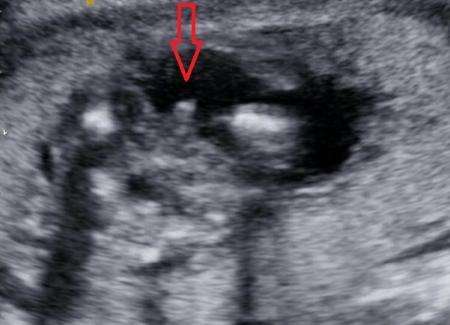

Hallo! Kann auf Eurem Ultraschall leider auch nicht viel erkennen. Finde es immer schwierig bei US-Bildern etwas zu erkennen, wenn man nicht selbst dabei gewesen ist. Kann Dir nur zum Vergleich mein US Bild anbieten. Das ist von 17+2 (SSW 18). Hab auch extra einen Pfeil eingefügt, um auf den vermeintlichen ,,Schniepi" im Querschnitt zu zeigen ;) Mein FA meint jedenfalls, das wird ein Junge. Aber ich werde die nächsten Untersuchungen noch abwarten... hätte den Beweis gern in 3D :))

Bild zu